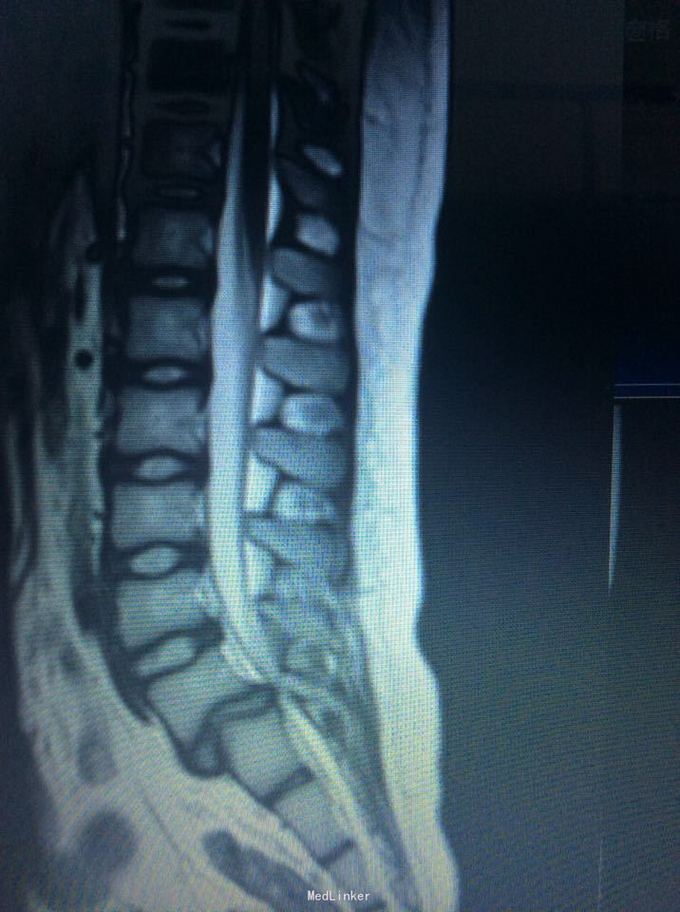

腰椎滑脱

椎体滑脱

9岁,腰痛一年

术前joa 评分17分

腰5椎体滑脱ii度 后路椎弓根钉椎间自体髂骨融合